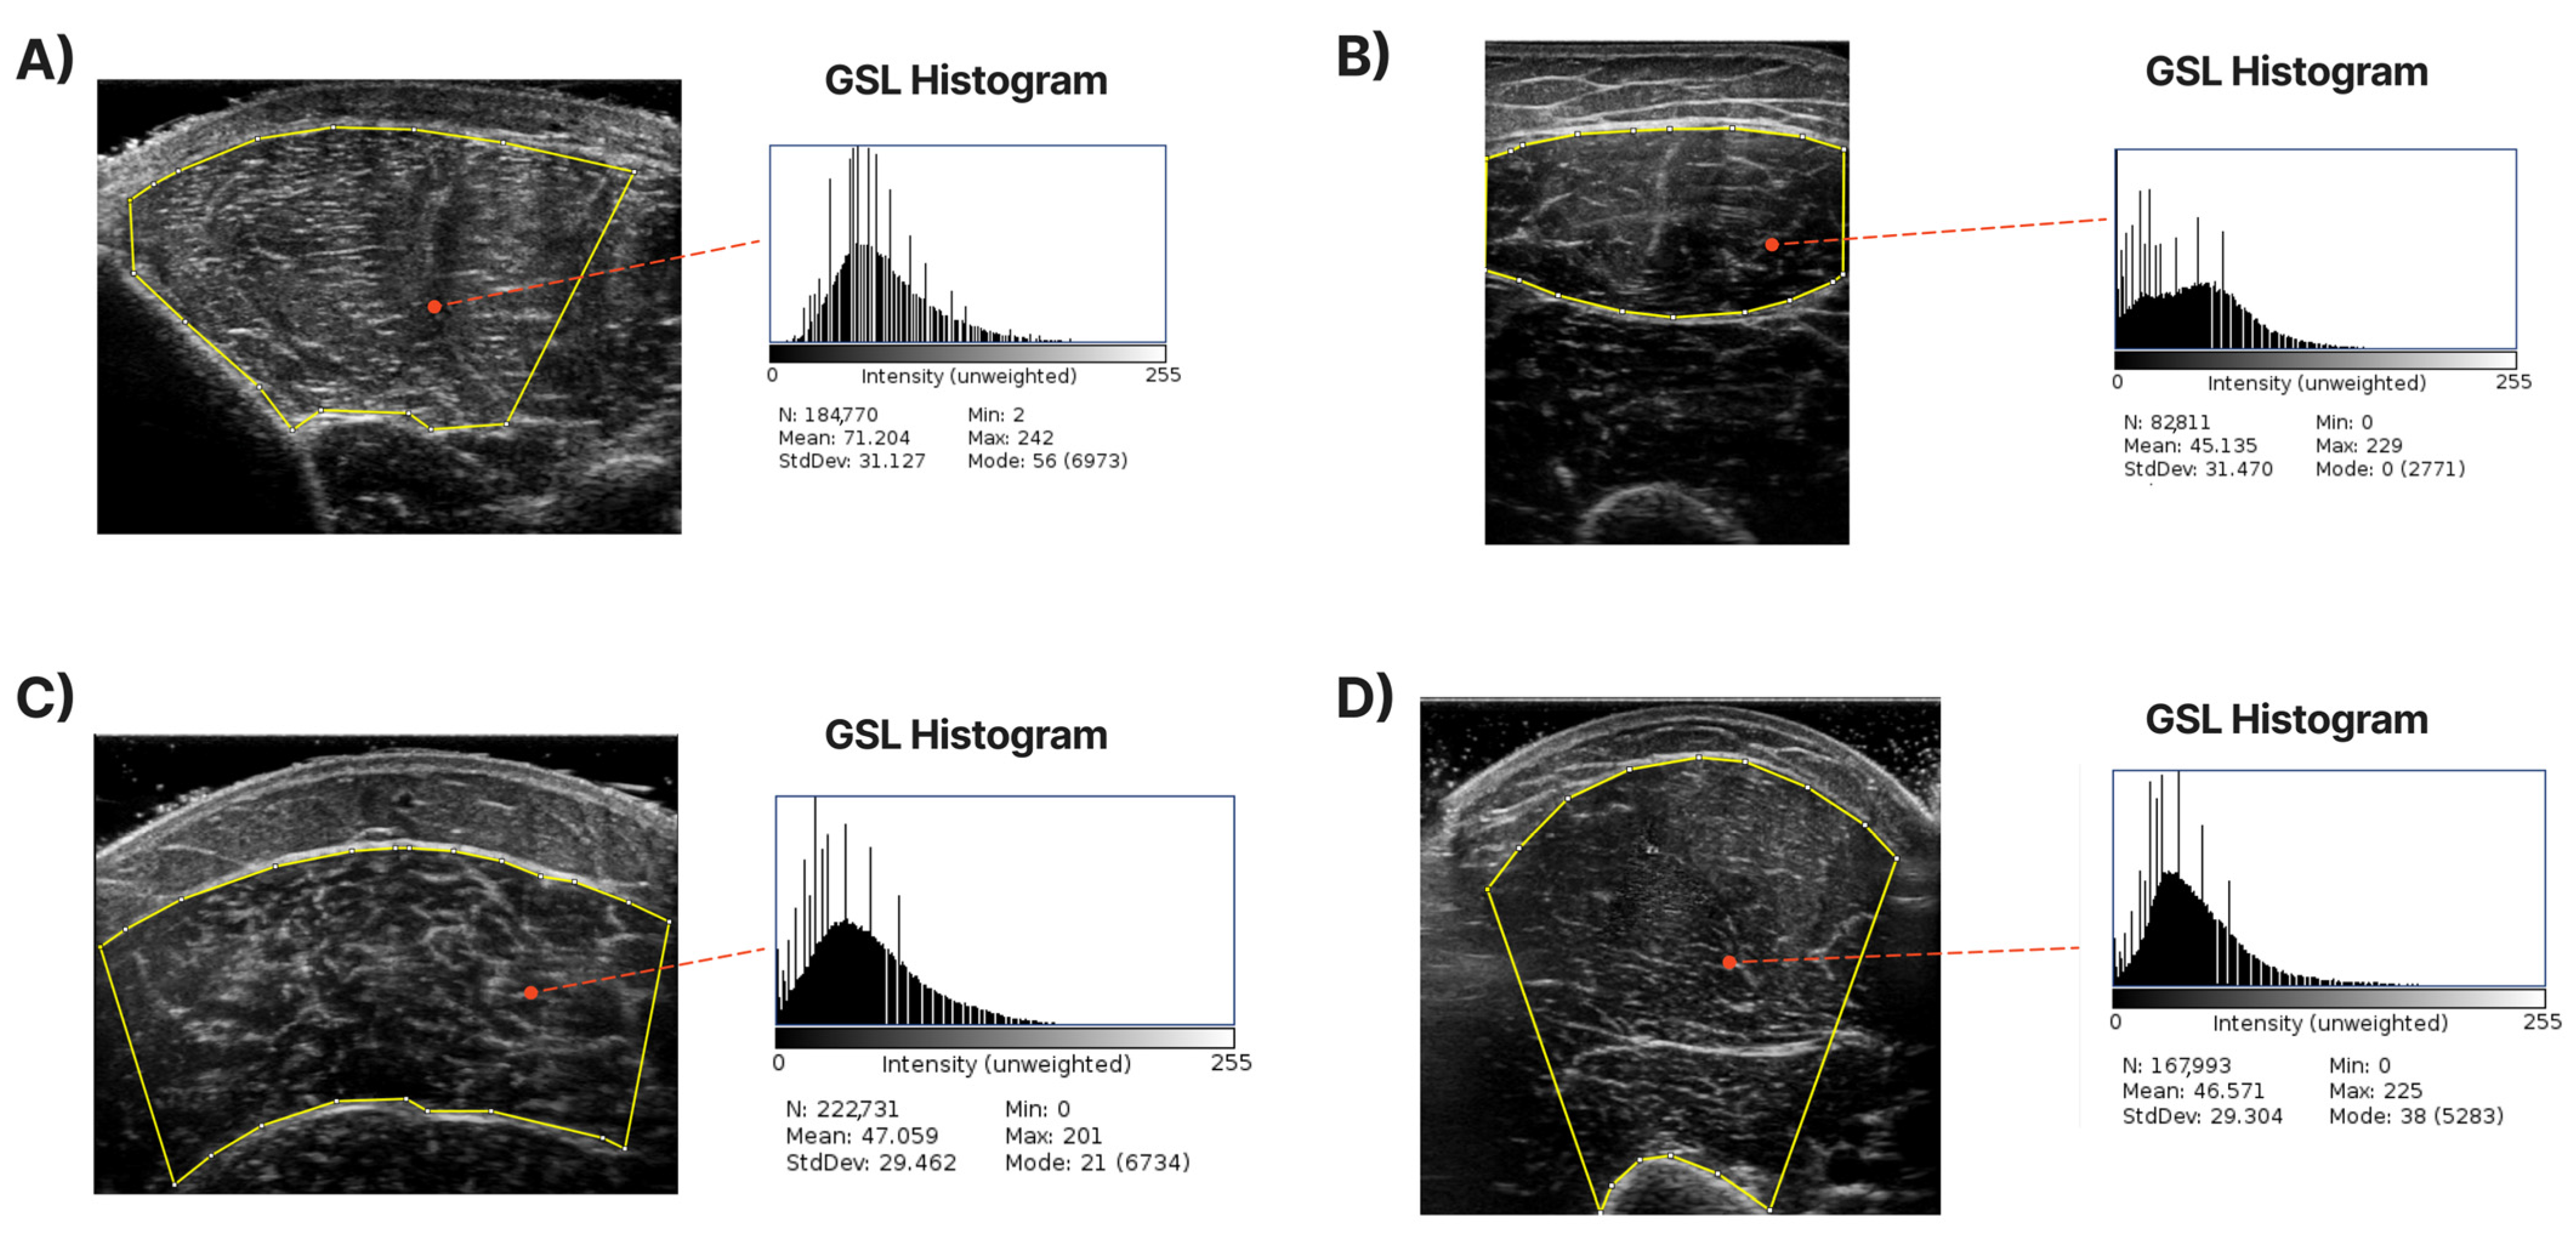

An accurate definition of the CSA in each examined muscle is required to develop a system to extract it automatically. For each muscle, the expert has annotated the maximum visible cross-sectional area (highlighted with the yellow contour in the images of Figure 2) based on his experience but also following the guidelines presented in [4,11]. Specifically, for the T.A., R.F., and B.B., the transverse recording was sufficient to capture the entire muscle in most cases. For the GCM, the whole visible part of the muscle was labelled as the CSA. We tried to omit the areas near edges where artefacts existed since they do not accurately represent the inner muscle and can cause deterioration in the accuracy of muscle echogenicity measurements. In Figure 2, some images, along with their annotated counterparts, are presented. Finally, from the pixels inside the CSA, the mean grayscale level value was calculated to represent the muscle echogenicity as a singular value. This mean ( µ ) was calculated from the following formula:

Figure 2. Sample of ultrasound images with their corresponding annotation. The CSA area contours are depicted with yellow lines. The grayscale level (GSL) histogram and its mean value are extracted inside the CSA. (A) shows the measurements of T.A., (B) shows the measurements of R.F., (C) shows the measurements of the GCM, and (D) demonstrates B.B.